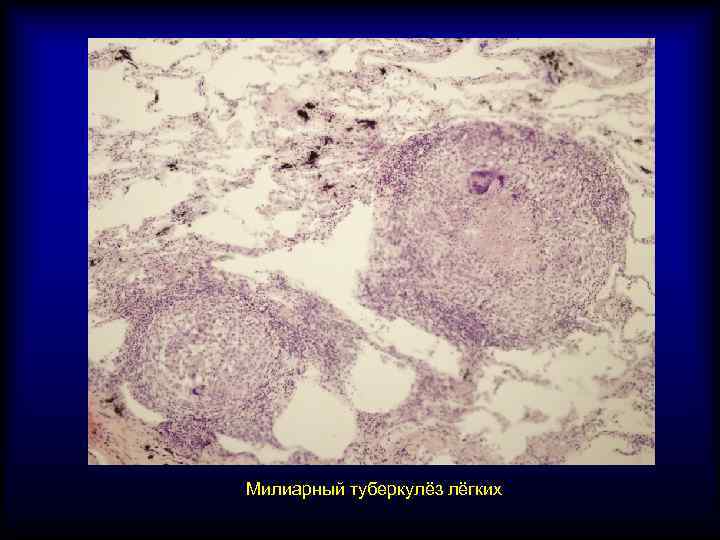

Микроскопический взгляд на мишитарный туберкулез легкого: фотодокументация

Раздел: Снимки-откровения